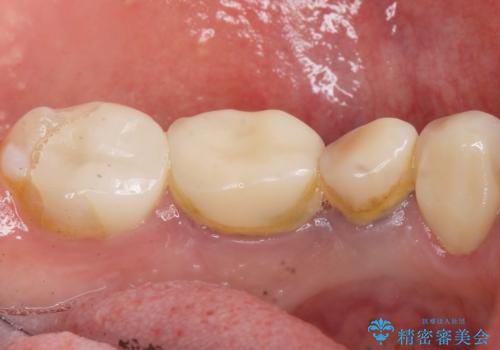

- 他院で奥歯に虫歯があると言われて、ご来院された患者様です。チェックしたところ、奥歯に虫歯は認められませんでした。

患者様は、もともと奥歯の虫歯を心配してご来院されましたが、前歯に問題が見つかりました。

金属を使用したメタルボンドクラウンが入っていたため、いつかオールセラミックにしたいときに根管治療も行ったほうが良いとご提案し、今回行いました。

就寝時マウスピース(約5000円別途)の使用をおすすめしました。